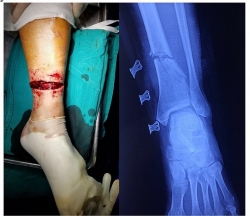

Hoà Bình: Người đàn ông bị lưỡi cưa máy cắt cỏ lia gần đứt rời chân

Đang sử dụng máy cắt cỏ, không may lưỡi cưa bị vấp vào viên đá văng ngược vào chân khiến ông B.V.L gần như đứt rời cổ chân.